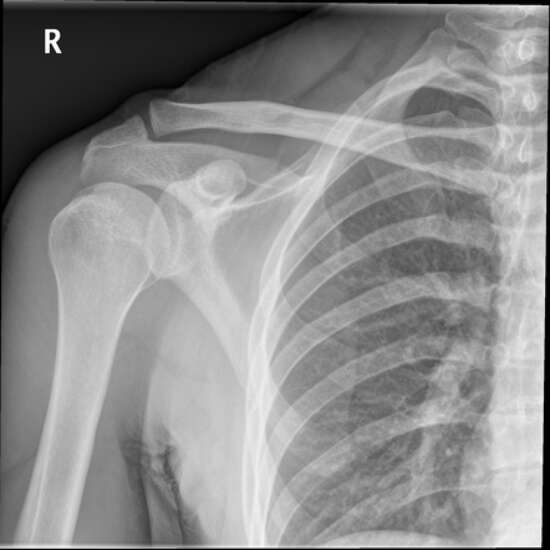

The shoulder joint, the collar bone (clavicle), the shoulder blade (scapula), the bone of the upper arm (head of the humerus), and the soft tissues (skin and muscles) that surround it can all be visualized using an X-ray of the shoulder.

The doctor will prescribe this test to diagnose any possible shoulder dislocation, frozen shoulder, or arthritis in this joint and monitor the healing process of a broken shoulder once it has been set.